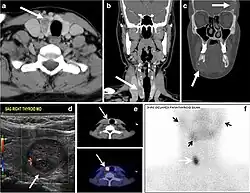

Fig. 7. A 51-year-old female patient post total thyroidectomy for PTC with elevated thyroglobulin measurement. an Axial non-enhanced CT scan of the neck at the level of the thyroid bed demonstrates a well-defined, rounded, homogenously dense soft tissue situated between the trachea and left internal jugular vein (white arrow). b Transverse ultrasound image of the neck demonstrates a well-defined, homogeneous, hypoechoic soft tissue nodule measuring 6 mm (white arrow) with no detected micro-calcifications. Biopsy showed a predominantly residual normal thyroid tissue with micro-foci of PTC.[1] -

Fig. 8. A 48-year-old male patient post total thyroidectomy with PTC recurrence. a Transverse greyscale ultrasound of the neck demonstrates a left thyroid bed heterogeneous, predominantly hypoechoic irregular lesion with calcifications (white arrow). b A spot image of iodine 123 total body scan of the neck demonstrate a focus of abnormal radiotracer uptake at the left thyroid bed (Black arrows) between the annotated markers. c Enhanced axial CT scan of the neck demonstrates an enhancing large left thyroid bed mass (white arrow) with no calcifications. The lesion exerts a mass effect on the oesophagus (black arrow) and is inseparable from the trachea.[1] -

Fig. 9. A 58-year-old male patient with persistence PTC at thyroid bed with hypervascular nodal metastasis. a–c Transverse greyscale and colour Doppler neck ultrasound demonstrate hypoehoic soft tissue in the left thyroid bed (white arrow in a). There are a heterogeneous enlarged lymph nodes at level 2 and 3 with markedly increased vascularity (white arrow in b and c). d–f Enhanced axial CT images of the neck demonstrate a 2.7 × 1.4 cm hypodense soft tissue lesion anterior to the left carotid sheath (white arrow). There are left-sided enhancing abnormal and enlarged lymph nodes at cervical level 2 and 3 (black arrows).[1]